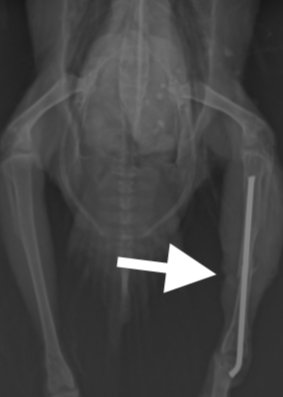

約3週間経過したところで、骨の状態をレントゲンで再チェックし、仮骨形成を確認した後、ピンを抜く処置をしました。ピンを抜いた直後もしっかり足を動かしてました。